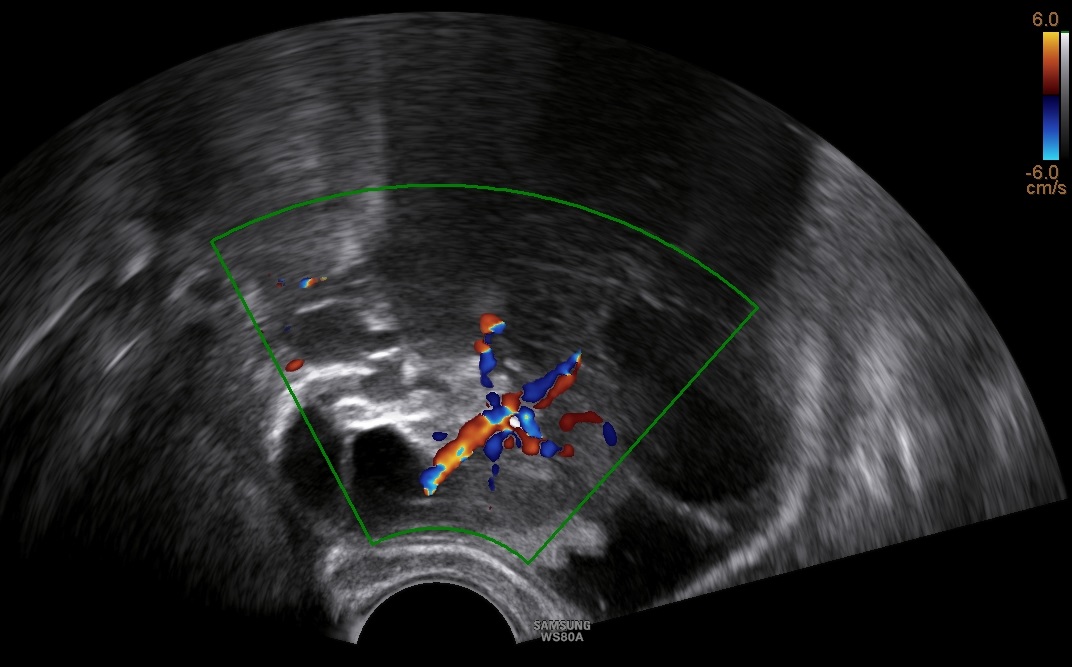

- 31-year old P1 with unilateral, 11.5cm large, multilocular, cystic ovarian tumor with solid components up to 4.2cm cointaining feeding vessels in doppler-sonography. CA-125 was negative. The patient desired further future pregnancies.